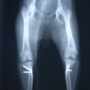

■ 症例20 ポメラニアン 8ヶ月 1.8kg

左右膝蓋骨脱臼 グレードⅢ

2ヶ月前から間欠的跛行が認められ、両膝の膝蓋骨脱臼整復術を行った。

手技は縫工筋及び内側広筋の解放、脛骨粗面の外側転位、滑車ブロック形造溝術、内外側関節包の縫縮を選択し実施した。

右側の膝蓋骨脱臼は上記手技で整復されたものの、左側はそれのみでは膝蓋骨が浮く様子が認められた。その為、PDS縫合糸にて膝蓋靱帯を1糸のみ縫合し、靱帯の縫縮を行った。

膝蓋骨脱臼は膝関節における膝蓋骨の内外側の脱臼と定義されるが、時として単純な内外の脱臼ではなく、膝蓋骨が大きく前方に浮き上がるように脱臼する場合がある。特にトイプードルやポメラニアンといった犬種に多く認められる。

内側脱臼に加えて前方への浮き上がりを矯正する為に、従来より脛骨粗面転移により膝蓋靭帯を外方と下方に引っ張り、固定する方法を選択する。膝蓋骨の前方への浮き上がりが軽度の場合は、従来法ではなく関節包の縫縮で対応していた。しかし、一部の症例で膝蓋骨の動きが悪くなり伸展機構が円滑に機能せずロボット様歩行になるケースがあった。

その為、膝蓋靭帯自体を縫縮する方法を採用した。この方法により、膝関節の伸展機構を妨げず膝蓋骨の軽度の浮きを矯正することが可能となった。

本症例の経過は良好である